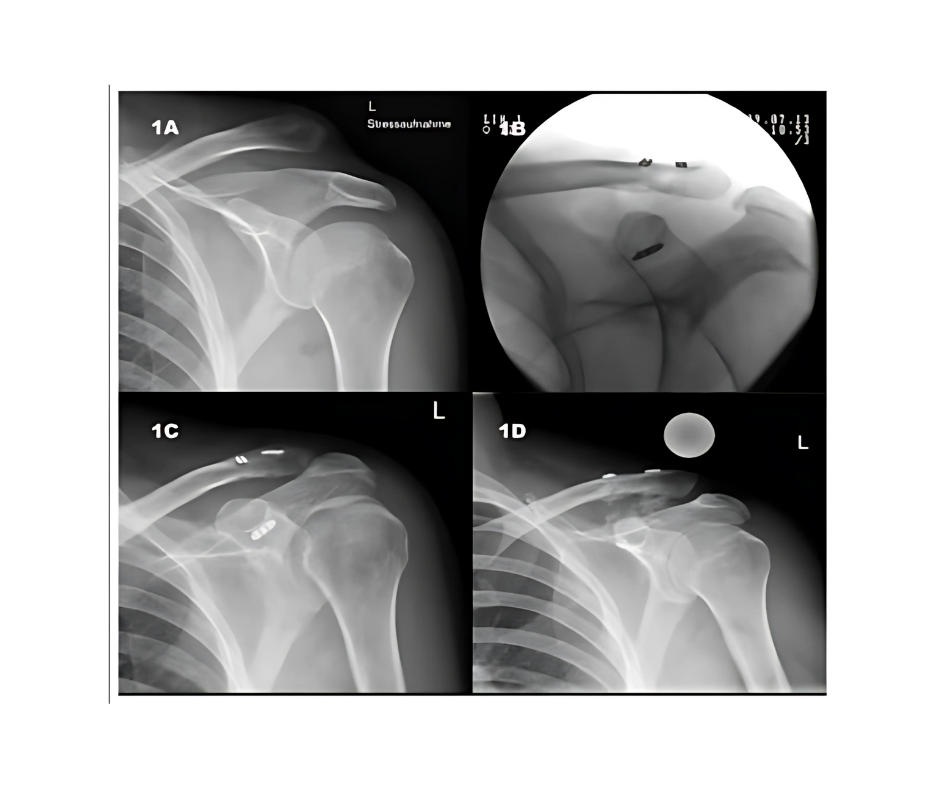

Sistema para luxación acromioclavicular

Es un sistema que le permite al especialista trabajar de forma segura, rápida y precisa, gracias a su técnica mínimamente invasiva y a su diseño que favorece la estabilidad ósea mientras protege las estructuras neurovasculares.

– Placa anatómica precontorneada, medidas 4 x 12

– Fabricada en Titanio de alta resistencia